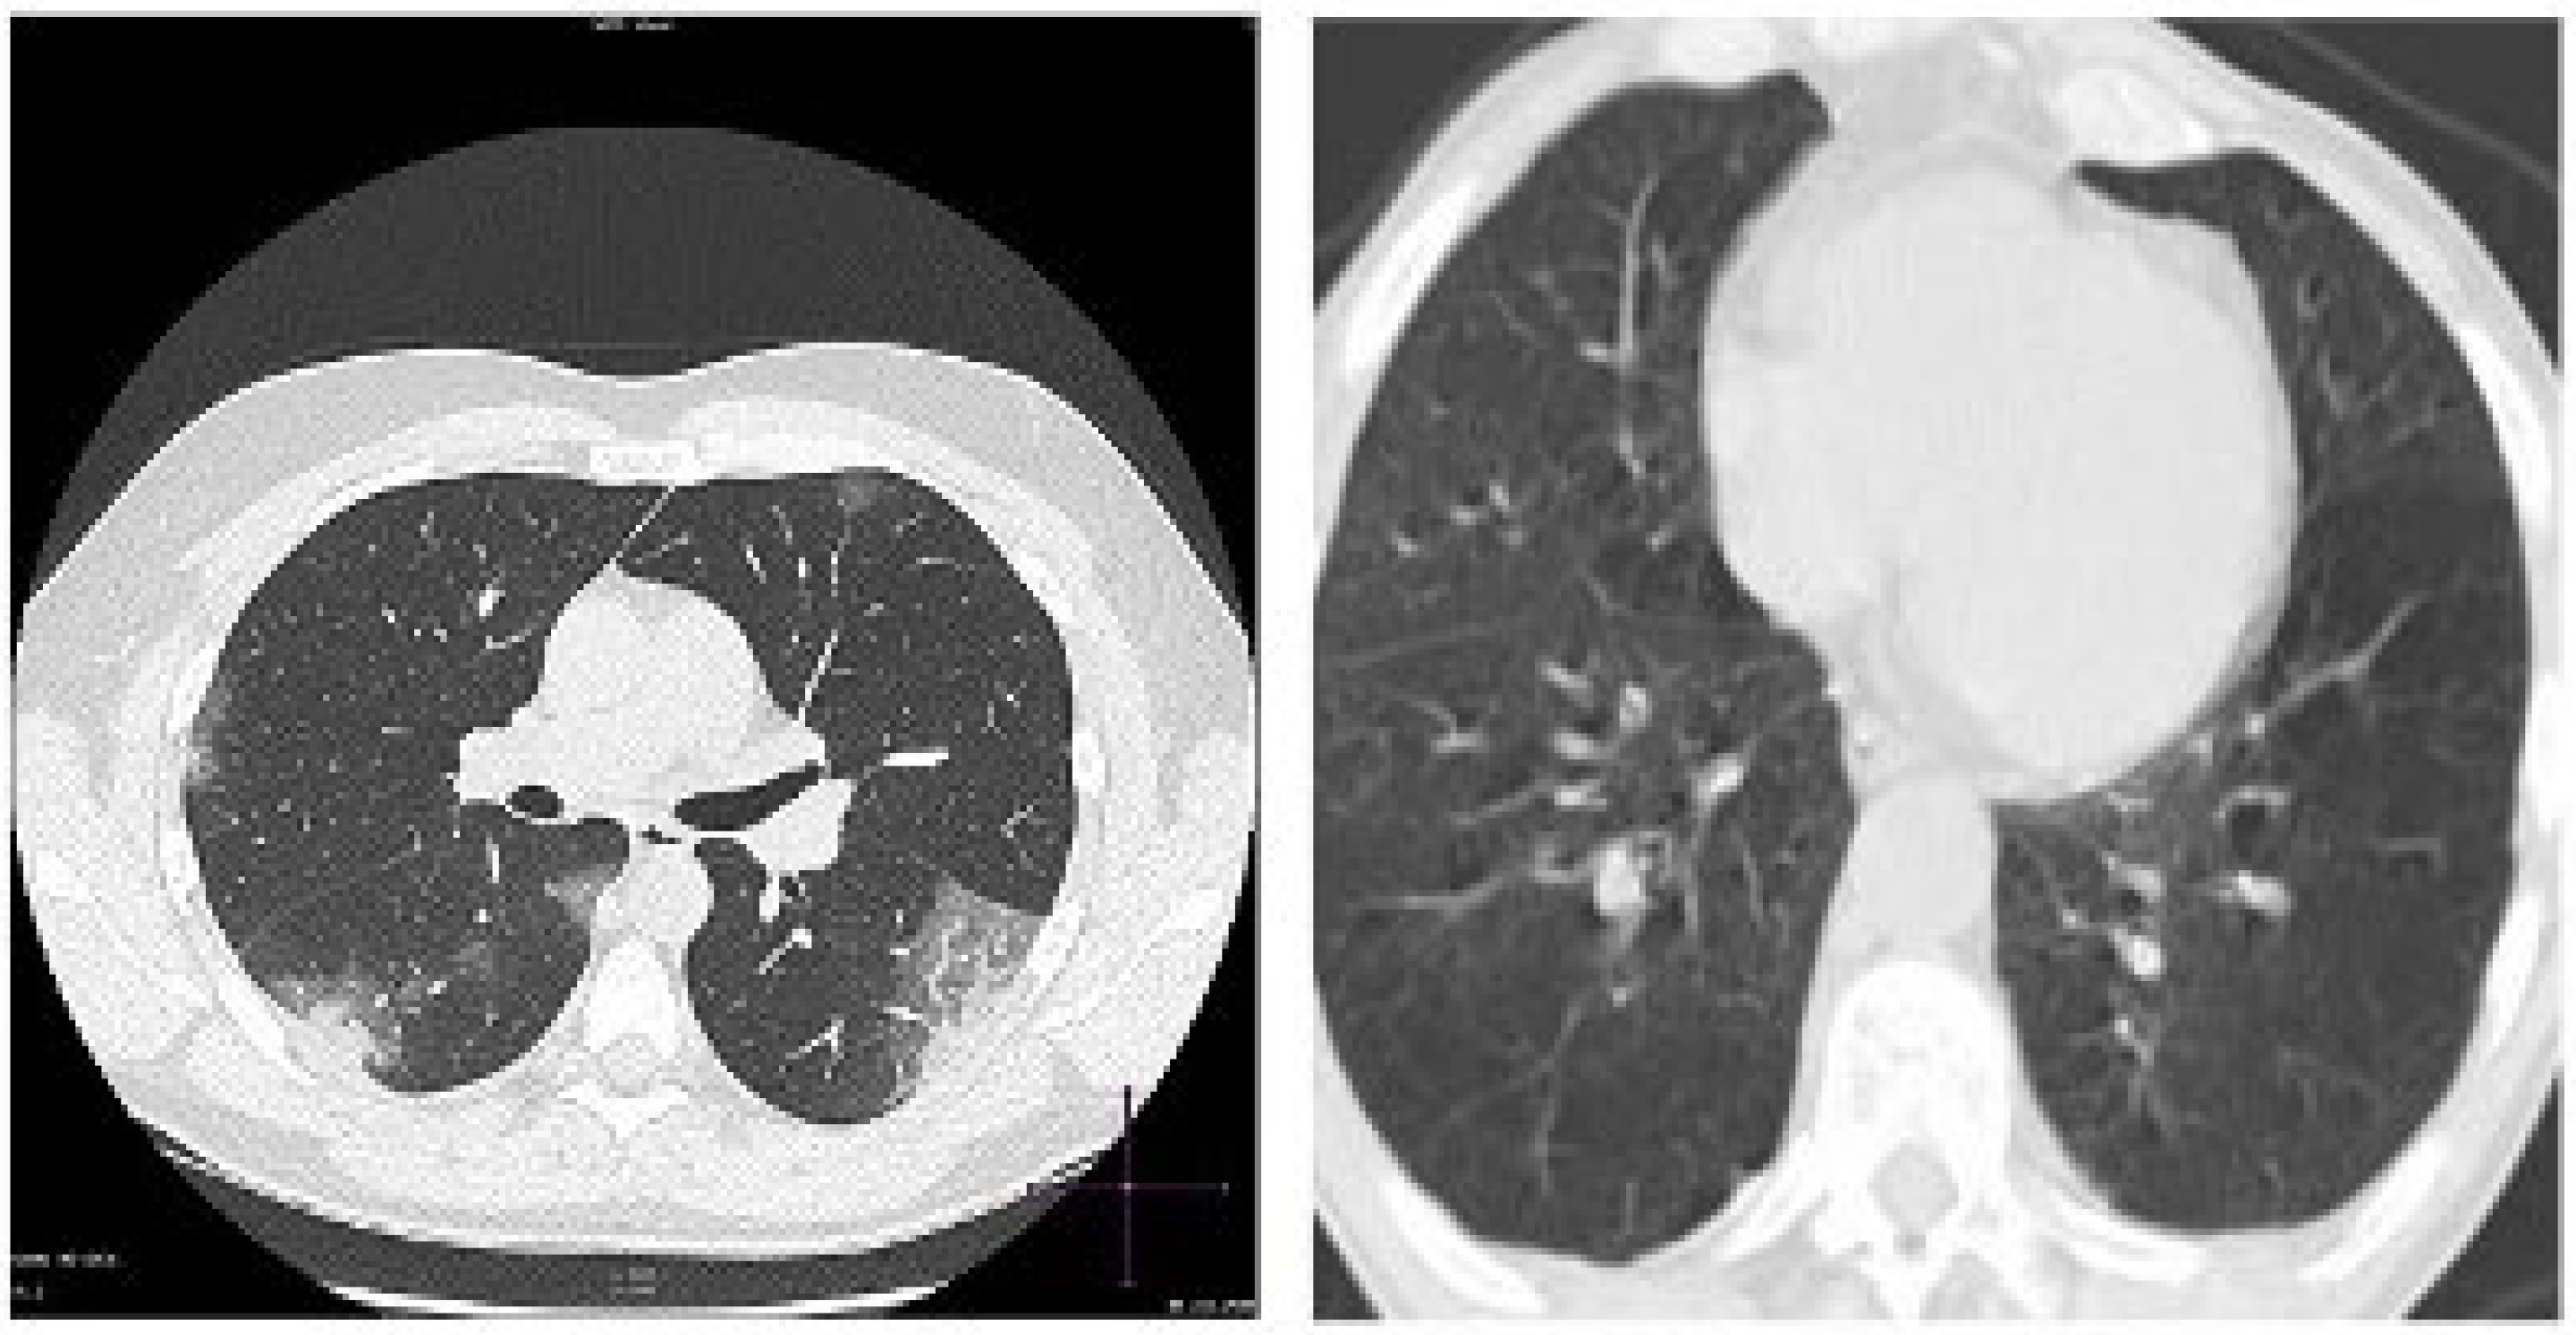

CT scan imaging modality is perceived by many scientists as the most efficient technique for screening for pulmonary diseases. One of the major differences between the CT scan machine and the X-ray machine is that X-ray machine uses a very small amount of radiation. The CT scan is more detailed, as it provides 3D images of tissues and organs, while X-ray provides 2D images. CT scan has shown to be more effective and sensitive in terms of imaging the chest, with outstanding spatial resolution. However, the limiting factors of using CT scan machine include exposure to high radiation and high cost [92]. The images of COVID-19 and normal cases are presented in Figure 6.

Figure 6.

CT scan Image. Left: COVID-19. Right: Normal.